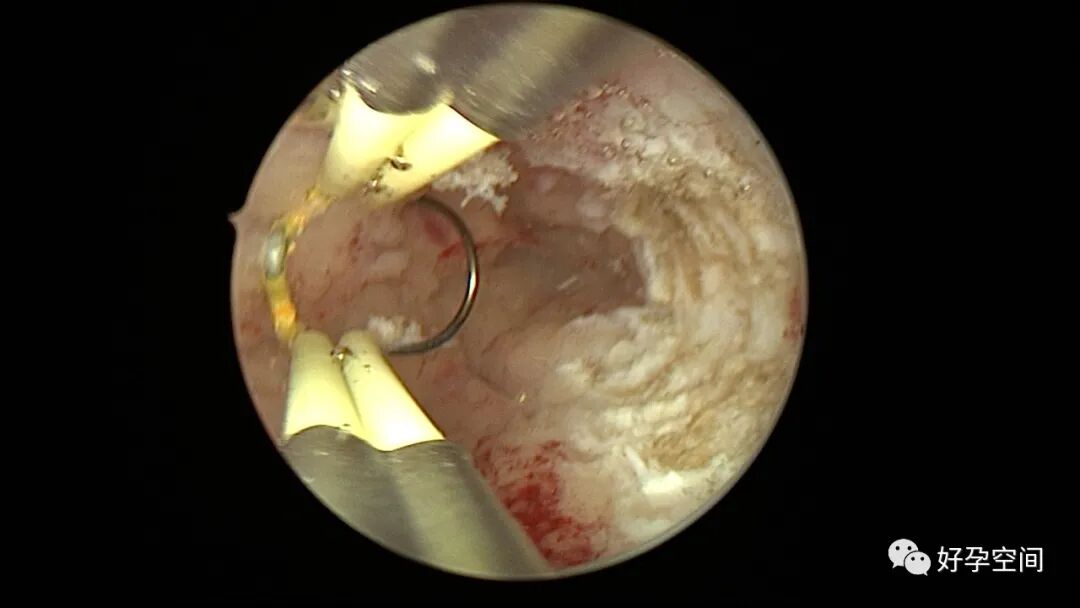

病例2:患者31岁,原发不孕,2019年11月在重庆某妇幼保健院做宫腹腔镜手术疏通输卵管,术中未取内膜活检,术后未孕。2021年7月在成都某大型生殖中心试管怀孕双胎(移植前未做宫腔镜检查及内膜活检),2021年11月孕4月双胎破水,在达州当地医院引产清宫,清宫术后40天复诊B超提示宫腔胚物残留。2022年1月到我院(眉山蕴缨妇产医院)行宫腔镜手术切除残留组织,2022年4月宫腔镜术后3个月复诊B超提示宫腔粘连,再次来我院行宫腔镜分粘。宫腔被覆一层沙丘状质脆增生组织,宫腔下段两侧壁内聚,行分粘术,取内膜送病检。

子宫内膜结核是由结核分枝杆菌在子宫内膜部位种植引起的炎症,是仅次于输卵管结核的常见女性生殖器结核。子宫内膜结核常由输卵管结核蔓延而来,多继发于盆腔腹膜结核或肺结核。子宫内膜结核的超声表现主要为:子宫内膜回声不均匀、宫腔内结节样病灶、宫腔内强回声灶、单纯的子宫内膜薄等。盆腹腔超声显示输卵管炎性表现:输卵管增粗、肥厚、扭曲、僵硬、输卵管积液积脓、卵巢旁混合性包块、输卵管系膜囊肿、盆腔包裹性积液等。术中所见:盆腹腔组织粘连、盆腹腔粟粒样结节、结核球、脓肿等,输卵管伞端烟斗样外翻,输卵管内充满淡黄色干酪样或豆渣样组织。宫腔镜显示宫腔狭窄、宫壁僵硬、宫内膜肉芽肿样增生、内膜质脆易刮除、干酪样组织、脓液等。

温宝宁等将子宫内膜结核宫腔镜检查的镜下表现分为:①宫腔形态、大小正常,双侧输卵管开口可见,子宫内膜发红、增厚,局部突起,表面可见少量质脆的小颗粒状赘生物,可刮出质脆的子宫内膜组织;②宫腔形态正常,但是宫腔内无正常子宫内膜,均被覆一层苍白的绒毛状或棉絮状质脆组织,血管少,无异形血管,宫腔内病灶与正常组织分界明显;③宫腔形态异常,呈窄桶状,子宫内膜瘢痕化,输卵管开口细小,甚至宫角消失。